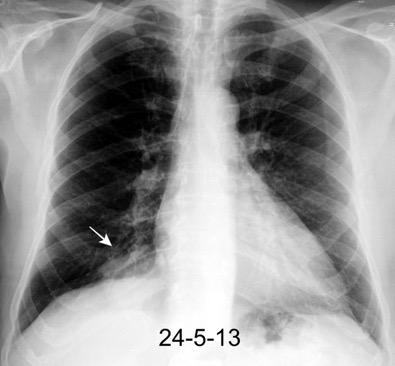

100. TUMOR FANTASMA

102. TUMOR FANTASMA. HEMATOCELE

En relación con trasudados tabicados. Insuficiencia cardiaca

Hipoalbuminemia

Cirrosis / Fallo renal.

Operado aneurisma (prótesis). Líquido tabicado en cisuras

Derrame pleural “encapsulado”

“Tumor fantasma”

Asociado a fallo cardiaco. ( “Pleuritis adhesiva”). Buch KP. Chest. 2000